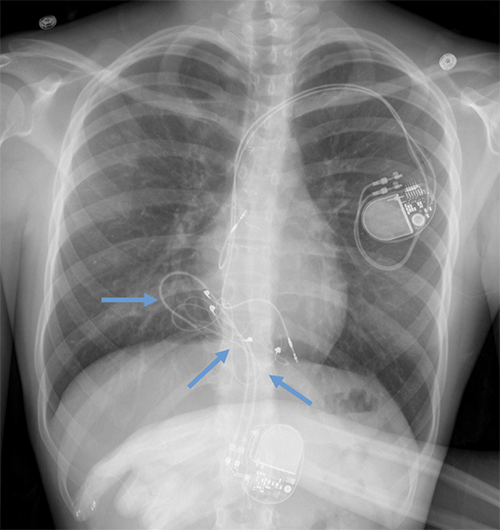

- CEID images with lead types:

Pacemaker with transvenous leads

Pacemaker with epicardial leads

Defibrillator lead

Subcutaneous defibrillator

Cut epicardial wires (often hard to see)

Abandoned leads

Abanded leads plus generator

Temporary transvenous lead

Leadless pacemaker